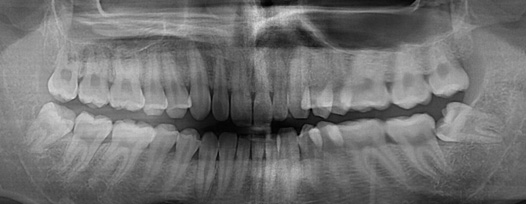

치주치료 전후사진

B

A